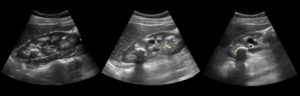

При проведении УЗИ почек можно увидеть расположение камня и его размеры.

Но стоит знать, что при помощи ультразвукового исследования камни в мочеточниках увидеть не удастся, поскольку они располагаются далеко в забрюшинном пространстве.

Камни на УЗИ в почках визуализируются достаточно хорошо. Именно поэтому такой вид диагностики является эталоном в урологии. Благодаря полученным результатам можно точно определить их количество, а также область локализации, что в последующем помогает в разработке лечебной схемы.

Если у пациента имеются солевые отложения, то камни в почках на УЗИ редко остаются незамеченными. Именно поэтому такой метод диагностики является эталонным. Однако выставлять окончательный диагноз и назначать лечение можно лишь с учетом других анализов и после осмотра пациента.

Вид нормальной почки с небольшими конкрементами на УЗИ. Источник: diagnoster.ru.jpg

Рассмотрим детальнее, как диагностировать камни в почках, если используется метод ультразвукового скрининга. Во время осмотра о наличии конкрементов говорит структура, характеризующаяся как гиперэхогенность, а также обладающая акустической тенью, размер ее должен быть не больше четырех миллиметров.

В некоторых ситуациях оксалаты, которые в диаметре имеют примерно 8-10 мм, могут не оставлять акустической тени. На УЗИ камень почки маленького размера, если используется цветовое доплеровское картирование, будет выражаться в виде артефакта мерцания позади.